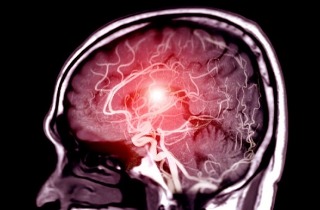

Medical News: Glioblastoma is one of the most aggressive and deadly forms of brain cancer, with limited treatment options and very poor survival rates. Now, new research suggests that metformin, a widely used and inexpensive diabetes drug, could help slow down this deadly cancer by switching off key survival signals inside tumor cells. Metformin may slow aggressive brain cancer by blocking ke...

Thailand Doctors: Glioblastoma, also known as glioblastoma multiforme (GBM), is one of the most aggressive and common types of primary brain tumors in adults. It originates from glial cells in the brain and is classified as a grade IV astrocytoma by the World Health Organization. This fast-growing cancer often infiltrates surrounding brain tissue, making complete removal challenging. Symptoms can ...